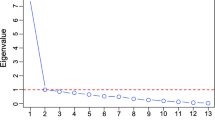

Random forest

Accuracy

This step was the preceding analysis to test the overall predictive accuracy of the models and their significance, which is a prerequisite for further random forest analyses. For the bilateral hippocampus and amygdala, the accuracy check revealed negative values for each model. Testing the accuracy of the models for prediction of the right and left ACC volumes revealed only one predictive model for each ROI, with model 1 predicting the right ACC volume and model 4 predicting left ACC volume.

For model 1, a model with basic CM characteristic scores, predicting right ACC volume, we found a positive, albeit small, accuracy R2 = 0.011 (p = 0.043). For model 4, a model with both type-specific timing values and basic neglect and abuse scores that predicted the left ACC volume, we found a positive, but also small accuracy R2 = 0.011 (p = 0.042).